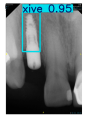

| Image Resolution = 825 × 1200 | ||||

| Test Image 1–4 | ![]() | ![]() | ![]() | ![]() |

| Accuracy | 94.13% | 95.29% | 92.88% | 91.80% |

| Recall | 96.71% | 94.03% | 93.88% | 92.15% |

| Model reference time | 6.57 ms | 7.08 ms | 7.12 ms | 6.43 ms |

| Dentists’ average diagnostic time | 2.78 s | 4.55 s | 7.78 s | 7.23 s |